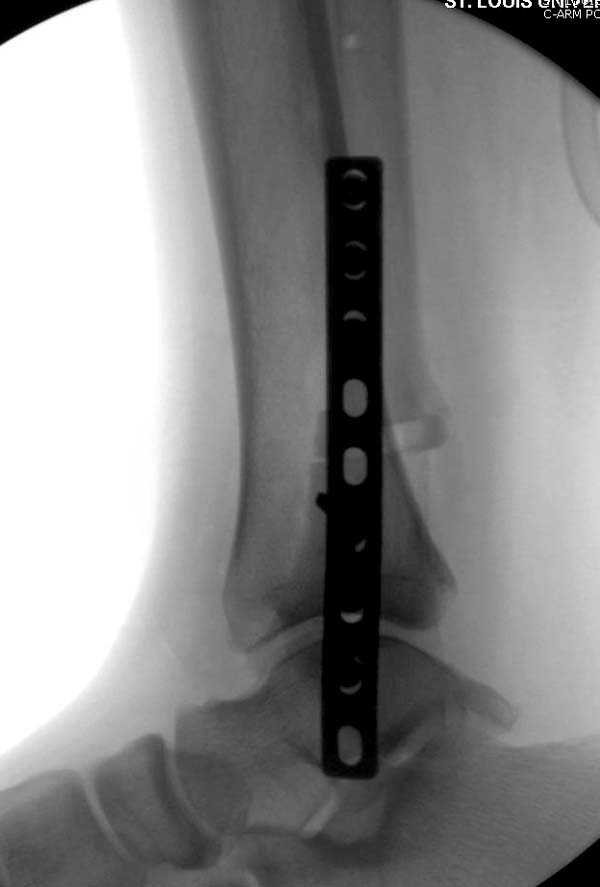

Проведена обычная стандартная процедура по исправлению неудовлетворительного состояния голеностопного сустава, где кроме удлинения малоберцовой с применением compression tension device за проксимальный конец пластины, проведено замещение трикортикальным графтом из крыла, освобождение синдесмоза и медиальной щели от

фибротических масс с фиксацией.